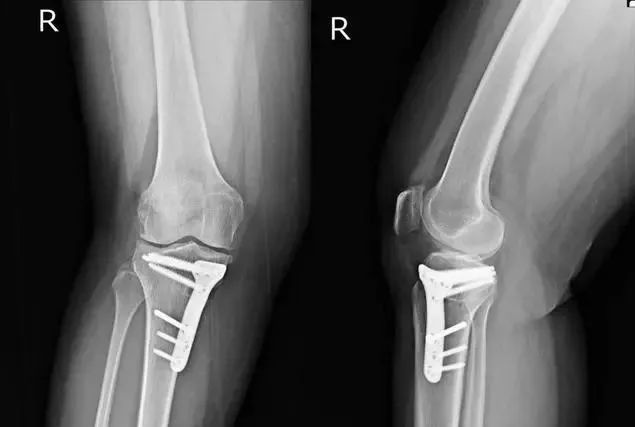

遇到了骨折患者术后钢板断裂,螺钉松动。面对这种情况,大多数患者会提出以下问题:“为什么这么结实的钢板会断”,“断了以后该怎么办?”

骨折或缺损后,植骨通常需要一个稳定的装置来连接骨头,并使其愈合。愈合应该有一个保证,这样骨头就不会移动。所以在这个时候,我们通常使用钢板来固定骨头的断端或缺陷。钢板一旦固定,骨头的上端、下端、远端和近端就会稳定在一起。

如果骨头已经完全愈合,钢板断裂,或螺钉松动,此时不需要处理,因为骨头已经生长,骨头的功能已经恢复。所以钢板或螺钉,此时没有更好的效果,你可以选择拆除钢板或螺钉。当然,如果骨骼愈合不是很彻底,而且还没有完全愈合,松动的螺钉应该重新固定。事实上,骨折的固定范围仍然有限,如简单的骨折,那么骨折上下,可能至少有两三个螺钉固定,所以钢板的距离是确定的,如7厘米,8厘米。然而,如果骨缺损,钢板可能会跨过缺损段,在近端骨和远端骨,然后至少固定三个螺钉,此时其长度会更长。固定长度越长,受外力影响的机会就越大,越容易断裂和松动。